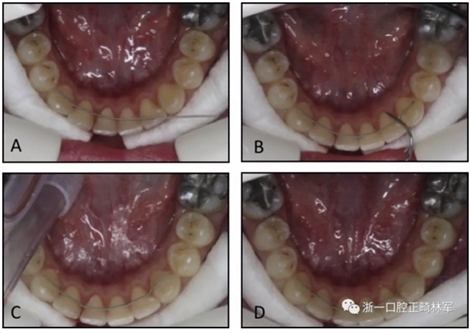

圖2. 第二組,在沒有石膏模型的情況下制備極軟的保持弓絲:A,極軟的保持弓絲與左側(cè)尖牙粘接; B-D,然后弓絲被動地適應(yīng)并粘接到其他牙齒。

在第二組中,保持器直接粘結(jié)。首先,用與第1組相同的粘接劑將極軟的保持弓絲粘接到左側(cè)尖牙上,然后將弓絲被動地與其他尖牙和切牙的舌側(cè)表面相適應(yīng)。極軟弓絲使臨床醫(yī)生能夠使用手持儀器輕松彎曲保持器(圖2)。下頜切牙和另一個尖牙用相同的粘接劑底漆和糊劑粘接。所有的保持器都由同一個擁有超過2年臨床經(jīng)驗的研究員(F.G.)粘接。在兩組拔牙患者中,保持器達到了第一前磨牙。兩組上頜牙弓均采用壓模保持器。